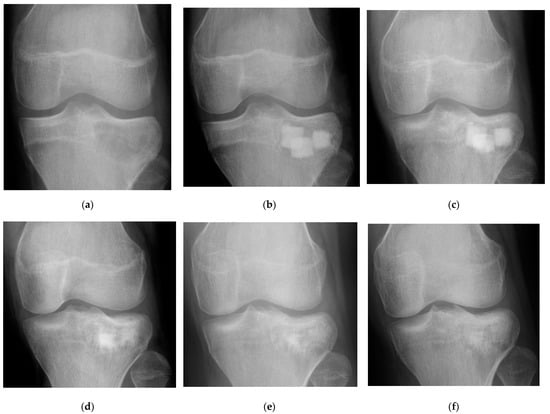

3.2. Radiographic Outcomes